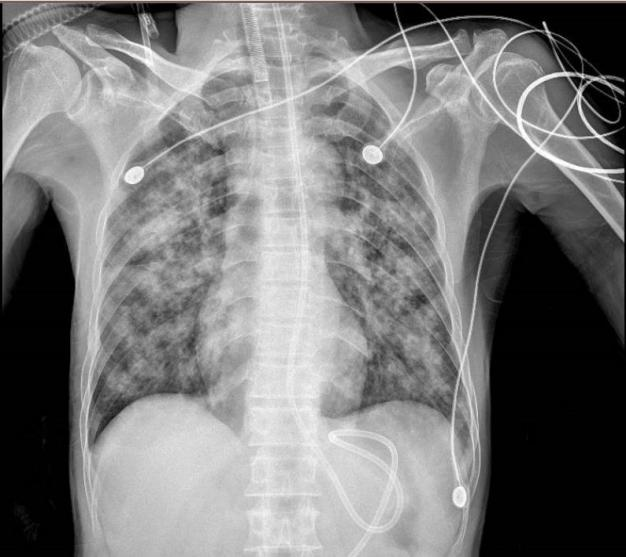

文章配图

治疗6天后复查胸部CT:双肺斑片状、絮状影及磨玻璃密度影明显吸收

在明确病因后,广州市第一人民医院呼吸与危重症医学科予患者以积极抗细菌、抗病毒、激素抗炎、抗凝、纠正溶血性贫血、免疫调节,保护脏器功能等综合治疗。随后,患者病情得到逐步控制,氧合指数好转,两边肺渗出也很快吸收,最终顺利脱离呼吸机。患者住院11天后顺利出院。